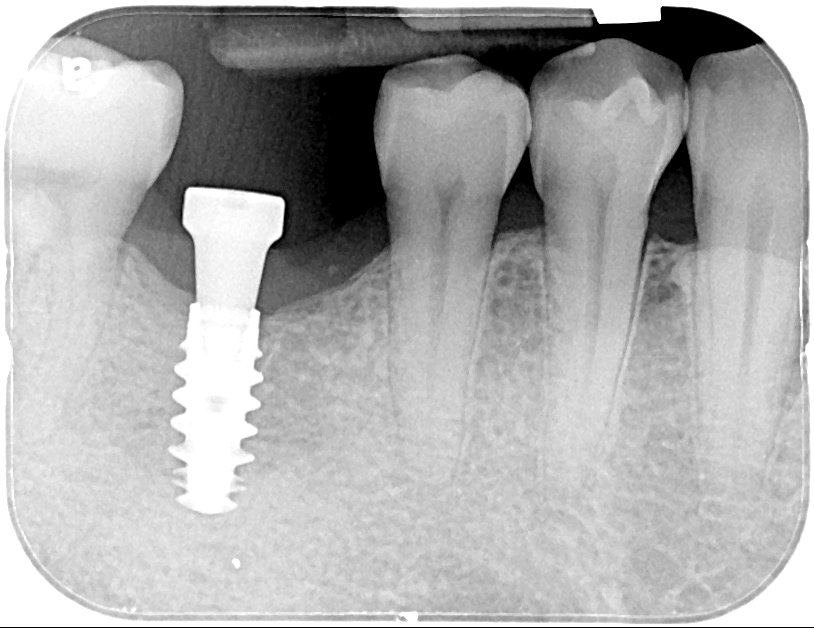

數位植牙的好處? 不管採取何種植牙治療方式,「4D微創導航系統」牙科技術能夠輔助醫師,在治療時,除了能透過醫師臨床的經驗與技術外,更能精準的控制與判斷病患的所有狀況,降低療程時可能發生的風險,以及減緩術後的不適感。 醫師會在病人的缺牙上,裝上一顆如同「監視器」的機器,搭配「4D動態導航系統」牙科技術,讓醫師在植牙的時候,能夠即時、精準的監測病人口腔骨頭內的狀況。 植牙有黃金治療時間嗎? 植牙的黃金治療期是「越來越快好!」為什麼是「越快越好呢?」最主要是因為牙齒與牙槽骨是相互依存的關係,當缺牙的第一年,骨頭會吸收得特別快,接下來每年以等比的速度吸收。 當口腔內的牙齒,有任何問題或是已經出現缺牙的情況,應該盡快尋求牙醫師的協助!進行治療與骨頭重建的需求評估,已避免增加重建的困難度,甚至無法治療。 到底適合「植牙」,還是要做利用兩邊牙齒做「牙橋」,最終還是需要經過醫師的專業判斷。 如何在茫茫醫海中,尋找適合的植牙醫師? 「一般牙科、贋復補綴科、口腔顎面外科、牙周專科」現代人很喜歡上網做功課,但想要找植牙醫師時,卻不知道從何尋找到適合的植牙醫師。 其實,能夠提供患者專業植牙技術的醫師,通常會受過「贋復補綴科、口腔顎面外科、牙周病科」這3大科的專業訓練。 擔心花錢後植牙出現問題又無法處理,如果長期看診的牙醫診所沒有相關的專業醫師,可以請醫師幫忙轉介。 另外,也可以挑選幾位自己喜歡的醫師,進行面診諮詢,找出最適合的醫師。最後,與醫師充分的溝通、配合也是植牙成功與否的重要關鍵。 植牙的步驟 植牙的流程大致可以分為幾個階段:資料蒐集、資料分析與重建理想牙位、植牙手術與植牙臨時假牙製作,以及最後最重要的植牙假牙製作。 植牙諮詢的第一步「資料蒐集」 資料蒐集、分析: 先利用口腔掃描機、臉部掃描儀、X光片、斷層掃描等,蒐集病患口腔整體環境、牙齦、骨頭的臨床資訊,以及紀錄顳顎關節與咬合的情況。 植牙手術 植牙手術:在經過專業的醫療團隊,進行術前評估後,以及擬定個人化的治療方針後,就會進入植牙手術的步驟,手術的步驟,會先進行牙齦翻瓣、鑽孔、植入人工牙根、縫合、拆線等。 不少人聽到上述步驟,或許已經頭皮發麻,專業的醫療團隊在治療的過程中,會搭配「舒眠麻醉」治療,能夠降低病患在過程中的不適感與恐聚感。 而通常人工牙根的癒合期大約需要6-12週的癒合,待癒合後才會進入「植牙臨時假牙製作」的製作。 植牙永久有效? 植牙有保固期 ? 「植牙成功後,就一勞永逸了嗎?就不用與醫師相見了嗎?」植牙它是鈦金屬釘子,植入骨頭癒合後,它不會蛀牙。但是,植牙周圍的牙肉跟骨頭,如果不妥善保養的話,還是會導致牙周病的發生,就是所謂的植體周圍炎。 植牙上方接出的牙冠,就好比買一台車,牙冠用久了,就如同車子用久了,零件、螺絲依舊會出現損毀的狀況,所以定期的回診保養追蹤是相當重要的。 通常植牙牙套完成後,至少半年回診一次,讓牙醫師檢查確認植牙附近牙齒沒有累積牙箘斑牙結石、植體周圍牙肉沒有發炎化膿,中間固定的螺絲沒有鬆動、牙套沒有破損、咬合狀況穩定等。 此外,患者必須維持良好的口腔清潔,可以參照之前我介紹的牙齒清潔方式,來保持好的口腔衛生、少抽菸等,如此搭配定期的回診檢查,可延長植體壽命。 植體的構造 植牙的治療過程很漫長,很多病患最常問的是「嘴巴內裝上的到底是什麼東西?」 今天的「植牙芯教室」就要帶你來認識「植牙整體的構造」(Dental implant) 口腔內的植牙由上→下依序是:牙冠、支台體、植體。 牙冠:又稱假牙冠、牙套,它是提供如同真牙的咀嚼功能,並且恢復美觀,永久性的牙冠最常見的材質為:全瓷、金屬合金、瓷熔合金屬。 支台齒:連接牙冠與植體的延伸部分,在中間點扮演重要角色,因為它必須要支撐牙冠的咬力,同時又要提供牙肉健康的生長環境,所以專科醫師在安裝時,必須依造病患口腔的狀況「客製化」的設計,ˊ尋找最適合的形狀、大小與角度。 植體:置入於缺牙的牙槽骨中,功能是取代原有的「牙根」,負責穩固牙齒的地基,目前最常見的植體材質為純鈦、鈦合金。 植牙x牙冠材質 對於越來越講求美觀的現代人來說,花錢植牙,當然希望它能美觀性與功能性兼具。 今天的「植牙芯教室」就要帶你來認識「牙冠材質」 目前,市面上永久性的牙冠最常見的材質為全瓷、金屬合金、瓷融合金屬 。 1.全瓷牙冠:材料有氧化鋯、強化玻璃瓷,不需要使用金屬,材質與人體的生物相容性高,同時具備高硬度的特性、高耐磨、耐高溫。在外觀上,呈色自然如同真牙,美觀性極佳。 2.瓷融合金屬牙冠:由於合金的成分複雜,若是高貴金屬的成分(黃金、白金)不夠高時,在口腔高溫潮溼的環境下,金屬容易腐蝕,導致表面粗糙,使牙菌斑難以徹底清潔,就容易造成牙齦發炎,並且染色,長期在美觀上、實用性都難以符合,對於外觀講求自然的病患。 3.金屬合金牙冠:由於整體採用金屬製作,所以不容易破裂、折斷,但是外觀呈現金屬色,所以當張開口時,便能夠一眼看出假牙的位置,如果使用金屬和金的牙冠,建議使用高貴金屬成分較高的材質。 植牙前的注意事項 想要提高植牙治療成功率,醫師與病患互相配合很重要,從術前的資料蒐集、評估與診斷,依據病人的情況,給予專屬的治療方針,從術中的治療過程,到術後的維護都非常重要,先來談談植牙前要注意那些事情。 1.保持口腔衛生:口腔清潔是植牙成功的最大關鍵 2.降低煙癮:抽菸會影響植牙的成功率,應該要盡量避免,如果能夠戒菸成功,更能提高植牙的成功率。 3.持續服用慢性病藥物:如果有在服用慢性病(高血壓、糖尿病等),在術前的諮詢,務必完整提供用藥歷史給醫師。 植牙後的潔牙步驟-工具篇 「植牙疏於潔牙與保健,百萬台幣立刻船過水無痕。」這是血淋淋的案例,真的不要以為,植牙完成後就一勞永逸。 術後的口腔清潔與維護非常重要!非常重要!非常重要!因為植牙的「使用壽命」,有非常大的關聯性。 植牙維護有三寶:牙刷、牙間刷、牙線 牙刷:可以選擇自己習慣的刷頭,或者選擇刷頭短小、刷毛軟硬適中的牙刷 牙間刷:當牙齦萎縮、牙縫變大時,應該選擇適合牙縫大小的牙間刷,用來清潔齒間的縫隙、牙套底層的牙菌斑與食物殘渣。 牙線:使用超級牙線,來清潔牙橋下的支柱牙部分。 漱口水、沖牙機等,這些只是輔助工具,千萬不能把它當作正規的潔牙器材。 植牙後的潔牙步驟-清潔篇 植牙的清潔方式。 首先:使用牙刷在假牙與牙肉的交界,採用刷牙法,來回輕刷至少10次。 接著:使用牙間刷,輕貼牙齒的表面,進行前後清洗,按照同一個方式,從舌側進入,輕貼牙齒表面,再做一次清潔,每次動作至少5次。 最後:使用大約45CM的牙線,可以使用穿引器的輔助,深入牙橋底下做清潔,每次動作至少5次。 植牙後的潔牙步驟-電動牙刷VS.一般牙刷 「做完牙套後可以用電動牙刷刷牙嗎?潔牙工具怎麼選?」上一篇,談了植牙的清潔方式,究竟植牙到底該不該用電動牙刷?答案是「可以」。 科學研究指出,使用電動牙刷,能更深入清潔到牙縫與牙齒倒凹處,尤其對於手部協調性沒那麼高的人,以及牙齒排列凌亂者,在清潔上能夠達到更好的效果。 刷頭的選擇:一樣要以刷頭小、刷毛軟硬度適中的刷頭,建議每1-3個月,或者外觀出現彎曲變形,刷頭就必須更換。千萬不要因為刷頭,比一般牙刷貴捨不得更換,反而會讓潔牙效果打折扣。 潔牙方式:電動牙刷與一般牙刷的潔牙方式的差異在於,電動牙刷只需要將刷頭輕放在單顆牙齒上,讓刷頭在牙齒與牙肉的交界處轉動,手不需要來回移動刷頭。但是千萬不要重壓,施壓過多的力道在牙齒上,反而對於牙齦是種傷害。 另外,不管使用電動牙刷或一般牙刷,都一定要使用牙線、牙間刷,來清潔牙齒與牙齒間的鄰接面,確保牙菌斑被清除。 潔牙時間:三餐飯後,30分鐘內如果能夠潔牙是最好的,如果無法達到,睡前徹底的潔牙是最重要!另外,潔牙時一定要有耐性,不要為了節省時間,隨便刷2.3下就結束。 如何選擇:預算、操作與攜帶方便度為首要考量,而且選擇具有「經濟部標準檢驗局」檢驗合格的產品,設計不良的電動牙刷,可能會造成口腔受傷。 植牙後的術後照護 植牙的最終成功與否,術後照顧真的非常重要!務必遵從醫囑,以下是照護的重點。 1.冰敷:術後1周,依舊會有些許的腫脹與輕微的瘀青,在48小時內,建議患者可以冰敷,在臉頰外側冰敷15-20分鐘,休息10分鐘,重覆動作到48小時。 2.不要泡溫泉、熱水澡,以及從事游泳與劇烈的運動。 3.飲食方面:初期還是會建議以流質、軟度高的食物為主,過燙、過冰的流質食物則不宜,應該避免食用過燙、辛辣、含有酒精成分刺激性的食物。 4.降低菸癮:為了讓植牙的傷口能順利恢復,醫學上皆有文獻記載,術後1周必須降低菸癮。 5.定期回診:植牙完成還是必須定期回診,讓醫師確認傷口、口腔健康的情形。 根據手術療程的不同,每一項術後的照護方式也有所差異,未來會跟大家分享與討論。 植牙後就能一勞永逸,不會有牙周病? 大多數的病患都知道,植牙前要先把牙周病及其他口內問題處理好,以降低口內細菌數量,才能夠進行植牙,但是很多病患以為,植牙成功,同時也能跟牙周病永久說再見,這觀念完全不正確。 簡單說「牙周病」是牙齒的周圍骨頭受到細菌的破壞,所造成的結果。因此,在植牙後,如果植體周遭的牙肉與骨頭,沒有得到妥善的清潔與照顧,還是會造成口腔內細菌的滋生,一樣會導致牙周病的發生。 植牙後,是不是也跟敏感性牙齒Say Bye Bye 一般所說的「敏感性牙齒」真正的學名是「牙本質知覺敏感症(Dentin Hypersensitivity)」會造成敏感性牙齒,主要原因是在於牙齒外層的琺瑯質被磨耗後,失去保護的功能; 或是牙齦萎縮牙根裸露時,都會造成牙本質內的神經小管暴露,當受到冷熱、吹氣、和壓力等刺激下,所產生的神經疼痛不適感。 植牙後,重建的人工牙冠內沒有神經,所以不會有敏感性牙齒的發生。然而,其他的自然牙齒,不會因為植牙而受到改變,當琺瑯質被破壞時,依舊會造成牙齒敏感性的問題。 骨質疏鬆的人適合植牙嗎? 「骨質疏鬆」有越來越年輕化的趨勢,除了因為年齡的增長之外,身體未獲得適當的保養也是元兇之一。如果是輕微的骨質疏鬆,只要適當的補充鈣質,想要植牙依舊沒有問題!整體還是必須交由專業醫師評估。 「骨鬆患者」,尤其是有在服用高劑量或施打抗蝕骨作用的藥物,是會影響植牙的成功率。原因在於,大多數的抗骨質疏鬆藥物,含有雙磷酸鹽,會影響骨骼細胞修補的功能,讓顎骨無法修復。所以如果有服用相關藥物,植牙前一定要告知醫師。 我是高血壓患者,能夠植牙嗎? 在高血壓控制好的前提下,是可以進行植牙手術的!正常的血壓是指收縮壓120/舒張壓80mmHg,當血壓偏高時,會增加手術中的出血狀況,提升手術的複雜度,甚至會提高手術後的感染率。 很多高血壓患者會服用「抗凝血藥物」。「抗凝血藥物」可能會在手術時,出現傷口流血不止的問題,所以醫師在進行植牙評估時,一定要讓醫師了解自身的慢性病史與用藥,並且盡可能尋找能提供詳細治療計畫,以及擅長微創植牙手術的醫師,降低植牙的風險。 我是糖尿病患者,能夠植牙嗎? 糖尿病患者與高血壓患者,都是在控制良好的前提下,能夠完成植牙手術。由於糖尿病控制不良的患者,細胞修復的能力與免疫系統,跟正常人比起來比較低,相對的牙周組織再生能力、傷口癒合情況也比較差。 所以想要植牙,必須同時與新陳代謝科醫師與植牙醫師相互合作,穩定血糖。除此之外,糖尿病患者也應該養成良好的口腔保健習慣,在經過醫師的專業評估,提供完善的治療計畫。 糖尿病與牙周病的關係? 「牙周病已經被列為糖尿病的併發症之一」前面談到「只要控制好血糖」依舊能夠植牙。我們也提到植牙前,一定要把牙周病控制住。今天我們就來談談「牙周病與糖尿病控制不良的關係」。 事實上,糖尿控制不良的病患發生牙周病的機率是正常人的3倍。最主要的原因,口腔細菌量會比正常人多,由於免疫系統比較差,更容易受到感染,所以傷口的復原能力也較低。 一旦糖尿病控制不良者得到牙周病時,病程也會跟著加速,骨頭被破壞與受損的速度也會加快。並且,因為身體長期發炎,將會導致血糖更不易控制。 癌症患者適合植牙嗎? 「癌症已經連續多年佔據國人10死因的首位」而癌症到底能不能進行植牙手術呢?首先,醫師會先了解病人的癌症種類與期數,以及過去的病史、治療史、用藥史,經由病人提供的資料,來做精準的判斷。 癌症的放射治療、免疫抑制等是會影響到傷口的癒合,治療上會使用到,抗骨吸收藥物 (antiresorptive agents)與抗血管生成藥物(antiangiogenic agent)等,都很有可能增加顎骨壞死的風險。另外,頭頸部經過放射線照射後,也會造成骨細胞的活性降低。 而且病人在接受化療、標靶藥物時,也會因為治療後,免疫力降低,細胞修復能力變弱,如果在治療期間,或是在治療後,想要做植牙,都應該先找醫師進行評估身體各項數值,以提高植牙成功率。 懷孕期間能夠植牙嗎? 雖然植牙是一個小手術,但是通常醫師都不會建議準媽咪們,在這時候進行植牙手術,首先,因為植牙是必須照X光檢查,在懷孕期間,應盡量避免暴露在輻射線下。 同時植牙必須經過麻醉的步驟,雖然麻藥會經由尿液排除體外,但大多數麻藥都含有「血管收縮劑」的成分,在治療過程中引發的加倍焦慮,可能會造成者子宮提前收縮的風險。所以會建議想植牙的準媽咪,產後再進行植牙手術。 產後、哺乳期植牙注意事項 「醫師,我正在哺乳期能植牙嗎?」在懷孕期間,就算已經完成第一階段的植牙手術,醫師為了保護母體與胎兒,會直接將療程暫停至產後,但是女性「產後要多久才能植牙?」、「哺乳期能植牙嗎?」成為許多媽媽最常問的問題。 事實上,女性產後的身體狀況恢復到一定的程度,就能夠進行植牙。而為了擔心麻醉藥或是抗生素、止痛藥分泌到母乳,加上每種藥物的半衰期不同,通常會建議,服用完最後一次藥物,在相隔24小時後,才進行哺乳。 服用健康食品是否會影響植牙 「維他命C、B群、魚油、銀杏、補鈣產品...」各式各樣的保健食品有吃有安心,很多病患到了診間,最常問我的問題之一「醫師,我有在服用各類的保健食品,會影響植牙嗎?」 事實上,需要看服用保健食品萃取的成分而定,不是所有的保養品食品,都會影響植牙的。如果營養品中含有「抗凝血作用」成分的保健食品,例如:銀杏、紅花。會建議在術前1周暫停服用。 雖然,適當的服用保健食品,確實有益於健康,但是在進行植牙評估時,還是務必告知,讓醫師做更正確的評估。 植牙要局部麻醉還是全身麻醉? 「植牙到底要全身麻醉,還是局部麻醉?麻醉的方式有哪些?差異性、有沒有後遺症?」許多病患都會有相同的疑問,從今天開始,一連串的文章來解惑。 其實,植牙手術跟一般口腔治療的方式一樣,能夠在病患清醒情況下進行治療,醫師通常會使用局部麻醉藥內含少比例血管收縮劑(Epinephrine),針對病人的手術內容,與治療所需的時間,給予準確的麻醉劑量。 由於大部分的局部麻醉藥,含有血管收縮劑,之前文章有提到高血壓的患者,必須在做治療諮詢時,提供用藥史與血壓控制情形,並且在手術當天,都應該接受血壓的測量,已確定用藥的安全性。 植牙的成功率?植牙失敗怎麼解?植牙的後遺症? 「植牙能100%成功嗎?植牙後是不是就再也不用回診?當植牙開始出現問題時,怎麼辦?植牙失敗後該如何治療?」這些問題是現在病患在選擇植牙時,很重要的考量。 「植牙成功率及植體壽命的長短」其實,最重要的是取決於醫師、病患有沒有合作無間,醫師與病患都應該在治療的過程中,扮演好彼此的角色,才能在植體成功骨整合後,延長使用的壽命。 病人,在諮詢時,要確實的將藥物史、病史提供給醫師。在治療期間,遵照醫囑、落實口腔衛生,並且在術後定期回診。此外,當植體出現任何情況時,必須立刻尋求醫師的協助「及早發現、及早治療」。 醫師,在技術、經驗上必須給予病患精準個人化的治療方針,並且選用大品牌的植體、生物醫材,提高治療成功率。同時,隨時吸收醫療新知,並將它運用,讓病患得到最好的治療。 上述都是植牙成功不可或缺的關鍵之一。 植牙後出狀況x牙冠瓷破裂 「植牙後出狀況怎麼辦?」 就如同之前所說,植牙就像是一部車子,用久了零件會出現受損的情況,要聊「出狀況怎麼辦?」就要回歸問題的根源來對症下藥,接下來,我將針對「植牙後常見的幾大狀況」來做詳細的說明: 牙冠瓷破裂:可將假牙取下,送修補瓷以回復美觀及咬合功能。因為牙科材料學的進步,新式二氧化鋯牙冠 (Zirconia),幾乎不會有破裂的狀況,這也是目前牙冠材質中,在品質與美觀上的表現,都擁有較高的穩定性。專業的贋復醫師在修復之前,會先把連接體跟牙冠中間的隙縫清潔乾淨,讓植體免於細菌感染的風險。 植牙後出狀況x植體配件的鬆脫、受損 「植體配件的鬆脫、受損」,之前的植牙芯教室,我們有介紹,牙冠與支台齒內含有各種不同的小零件,當植體用久了,零件開始出現狀況,該如何處理? 要談到該如何處置之前,要先了解,為什麼會發生「植體配件的鬆脫、受損」的狀況,大致可以把原因歸類為:零件壽命、植體長期咬合受力。 病患完成植牙後,在每半年的定期回診,牙醫師都會針對這些細部零件做確認,確定是否有鬆脫或晃動的情形出現。 一旦出現螺絲的鬆脫情況,沒有及時治療,螺絲就會斷裂在植體內,而要從植體內,將斷裂的螺絲取出,是件複雜又具高風險的療程,必須由經過專業訓練的植牙贋復科醫師來做處置,在往後的文章,將再做更詳細的說明。 植牙的麻醉方式有哪些? 「舒眠麻醉、全身麻醉、笑氣麻醉」這是目前大家在搜尋資料時,比較容尋找到的關鍵字,今天就來簡單介紹,這些麻醉的專有名詞。 舒眠麻醉:目前贋復科醫師最常使用的麻醉方式,屬於淺層麻醉,能夠讓病患在放鬆的情況下進行治療,也能夠降低局部麻醉的用藥量,關於「舒眠麻醉」接下來會一系列的介紹。 全身麻醉:屬於深度麻醉,麻醉藥的劑量會讓病患意識消失,而且無法自主呼吸,術後的恢復期較長,必須要在開刀房內進行。 笑氣麻醉:主要是用來鎮靜,而非麻醉,有些病患在做口內局部麻醉時,依舊會感受到看牙的緊張感,因此,有些醫院或診所,會備有笑氣設備,幫助病患在局部麻醉時,能夠鎮定。 植牙的評估要件懶人包 Q:缺牙會影響到那些層面? A:身體、心理都會受到影響,長期缺牙會讓導致「咬合障礙」 Q:到底要植牙,還是要做假牙? A:需要經過醫師的專業評估與判斷,「假牙」與「植牙」各有優、缺點。 Q:幾歲適合植牙? A:只要經過牙醫師臨床的評估,不管是25歲較年輕的缺牙病患,或者80歲的族群都能。 Q:如何在茫茫醫海中,尋找適合的植牙醫師? A:專業植牙技術的醫師通常會受過「贋復補綴科、口腔顎面外科、牙周病科」3大科的專業訓練。 Q:怕痛的人,如何進行植牙手術? A:現在也出現了「舒眠治療」,讓患者在治療上,大幅減低焦慮感。 Q:我是高血壓患者能植牙嗎? A:在高血壓控制好的前提下,是可以進行植牙手術的! Q:骨質疏鬆的人適合植牙嗎? A:如果是輕微的骨質疏鬆,只要適當的補充鈣質,想要植牙依舊沒有問題。 Q:癌症患者適合植牙嗎? A:在癌症治療期間或是在治療後,想要做植牙,都應該先找醫師進行評估身體各項數值,以提高植牙成功率。 Q:懷孕期間能夠植牙嗎? A:植牙必須經過麻醉的步驟,所以想植牙的準媽咪,產後再進行植牙手術。 Q:服用健康食品是否會影響植牙? A:需要看服用保健食品萃取的成分而定,不是所有的保養品食品,都會影響植牙的 舒眠治療懶人包 Q:舒眠治療有健保給付嗎? A:舒眠自療跟植牙如同屬於自費項目,並無健保給付。 Q:舒眠治療前需要做哪一些準備? A:由於治療藥物的濃度,與個人身體狀況與病史有關,所以患者必須確實告訴醫師用藥的習慣以及病史,必要時,在舒眠治療前,醫師會要求病患,先做身體健康檢查。 Q:平常有習慣吃保健食品需要暫停嗎? A:大部分的保健食品都不需要停藥。 Q:舒眠治療需要禁食嗎? A:需要的,必須至少禁食6-8小時,如果是在上午進行,前晚12時之後就不可飲食,如果是下午,則是早餐過後,就不能進食。 Q:舒眠治療前的禁食,若有需要服用藥物該怎麼辦? A:禁食期間,服用少量的水吃藥是被允許的。 Q:有服用抗凝血藥物怎麼辦? A:通常不需要停藥,除非是經過專業醫師指示,才需要停藥。 Q:舒眠治療當天可以駕駛嗎? A:舒眠完成後,可能會有頭暈的狀況出現,建議在親朋好友陪同下,搭乘交通工具前往診所。 Q:舒眠治療後的注意事項? A:在完成治療後,患者應休息20-30分鐘,確保沒有暈眩、嗜睡的情況發生,才能離開診所。 植體品牌 ║史得勞曼(Straumann)║ 瑞士的植牙品牌,經過許多臨床醫學研究證實,是植體品牌中邊緣骨流失最少的系統之一,其特殊植體連接體的設計,使牙冠與植體緊密結合,增加假牙的穩定度,降低鬆脫、晃動的機率。 →https://reurl.cc/8lDo1X ║諾保科(Nobel biocare)║ 瑞典的植牙品牌,在2008年推出的NobelActive系統,植體特殊的螺紋設計及表面處理,適用於骨質條件狀況比較複雜的患者。 →https://reurl.cc/xDN9zL ║亞仕特(Astra Tech Implant)║ 瑞典的植牙品牌,在植體與連結面的設計上,採用特殊的圓錐六角形內接式的設計,穩定的接口,能降低牙冠與支台齒,鬆脫的情形。 →https://reurl.cc/jd91bn ║百好(BIOHORIZONS)║ 來自美國的植體品牌,BioHorizons採用硬度、生物性較高的鈦合金材質,同時擁有特殊的Laser-lok專利技術,不僅能降低植體牙周病的發生機率,又達到兼顧美觀的功能。 →https://reurl.cc/YlYvZn ║貝格莎曼杜(BEGO Semados)║ 德國在地生根、製造生產超過125年的歷史悠久,植體表面特殊的TiPure技術,能夠幫助植體與齒槽骨結合,達到最大的整合功能,同時,也能幫助植體壽命的延長。 →https://reurl.cc/oD81ov” - 植牙後的保養 2026.01.19

X光檢查和電腦斷層掃描:

這些檢查可以幫助醫師更精確地了解患者的骨質密度和位置,以便進行更精確的手術規劃。